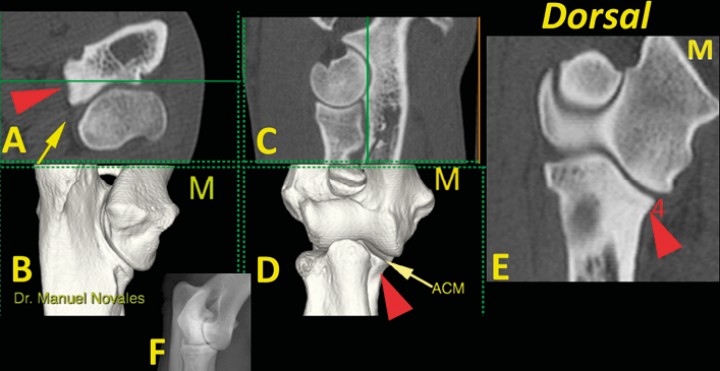

En el plano dorsal nos fijamos en tres zonas de corte concretas: a) la escotadura troclear del cúbito (Fig. 6); b) el ápex de la ACM, que debe ser cóncavo por su cara medial (Fig. 7); y c) la base de la ACM (Fig. 8). En este plano de corte debemos valorar: 5) ACM (mediante avance del corte dorsal para valorar una posible línea de fragmentación); 6) la unión completa de las caras medial y lateral del cóndilo humeral en su zona media; 7) la morfología normal del hueso subcondral del cóndilo humeral y su grado de esclerosis; 8) la congruencia articular humero-radial y húmero cubital; 9 y 10) y la ausencia de osteofitos o enteseofitos en las caras medial y lateral del codo (Figs. 7, 8 y 9) (Vídeo 3).

<p>Codo normal. Imágenes tridimensionales del codo en visión caudomedial (<strong>B</strong>) y craneal (<strong>D</strong>), así como planos de corte transversal (<strong>A</strong>), sagital (<strong>C</strong>) y dorsal (<strong>E</strong>). Las líneas verdes en A y C muestran el nivel al que se ha producido el plano dorsal (E). Se señala una escotadura normal (punta de flecha roja) que aparece en la porción medial de la ACM (flecha amarilla) (M: lado medial).</p>

Codo normal. Imágenes tridimensionales del codo en visión caudomedial (B) y craneal (D), así como planos de corte transversal (A), sagital (C) y dorsal (E). Las líneas verdes en A y C muestran el nivel al que se ha producido el plano dorsal (E). Se señala una escotadura normal (punta de flecha roja) que aparece en la porción medial de la ACM (flecha amarilla) (M: lado medial).

<p>Codo normal. Imágenes tridimensionales del codo en visión caudomedial (<strong>B</strong>) y craneal (<strong>D</strong>), así como planos de corte transversal (<strong>A</strong>), sagital (<strong>C</strong>) y dorsal (<strong>E</strong>). Las líneas verdes en A y C muestran el nivel al que se ha producido el plano dorsal (E). La punta de flecha roja señala la concavidad de la cara medial de la ACM (flecha amarilla) que debe ser de contorno liso (4). Se incluye una radiografía de codo en proyección craneomedial-caudolateral (F) para comparación. (M: lado medial).</p>

Codo normal. Imágenes tridimensionales del codo en visión caudomedial (B) y craneal (D), así como planos de corte transversal (A), sagital (C) y dorsal (E). Las líneas verdes en A y C muestran el nivel al que se ha producido el plano dorsal (E). La punta de flecha roja señala la concavidad de la cara medial de la ACM (flecha amarilla) que debe ser de contorno liso (4). Se incluye una radiografía de codo en proyección craneomedial-caudolateral (F) para comparación. (M: lado medial).

<p>Codo normal. Imágenes tridimensionales del codo en visión caudomedial (<strong>B</strong>) y craneal (<strong>D</strong>), así como planos de corte transversal (<strong>A</strong>), sagital (<strong>C</strong>) y dorsal (<strong>E</strong>). Las líneas verdes en A y C muestran el nivel al que se ha producido el plano dorsal (E). Se señala el ápex de la ACM (flecha amarilla). En este plano dorsal se valora: ACM (mediante avance del corte dorsal para valorar una posible línea de fragmentación) (5); la unión de las dos porciones del cóndilo humeral (6); la morfología normal del hueso subcondral de la porción medial del cóndilo del húmero y su grado de opacidad (7); la amplitud de los espacios articulares humero-radial y húmero-cubital (8); la ausencia de osteofitos o enteseofitos en las caras medial (9) o lateral (10) del codo. (M: lado medial).</p>

Codo normal. Imágenes tridimensionales del codo en visión caudomedial (B) y craneal (D), así como planos de corte transversal (A), sagital (C) y dorsal (E). Las líneas verdes en A y C muestran el nivel al que se ha producido el plano dorsal (E). Se señala el ápex de la ACM (flecha amarilla). En este plano dorsal se valora: ACM (mediante avance del corte dorsal para valorar una posible línea de fragmentación) (5); la unión de las dos porciones del cóndilo humeral (6); la morfología normal del hueso subcondral de la porción medial del cóndilo del húmero y su grado de opacidad (7); la amplitud de los espacios articulares humero-radial y húmero-cubital (8); la ausencia de osteofitos o enteseofitos en las caras medial (9) o lateral (10) del codo. (M: lado medial).